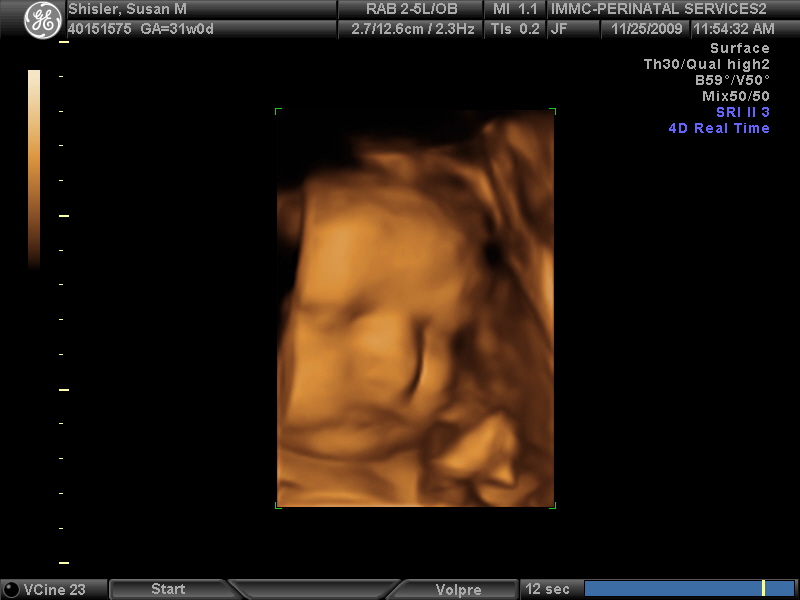

Baby